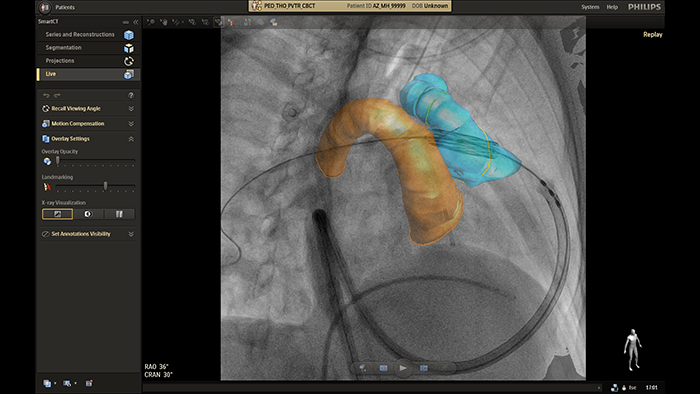

Guía en tiempo real de SmartCT

Cierre de la comunicación interauricular con fusión en tiempo real de EchoNavigator

Guía de colocación de stent en coartación aórtica con VesselNavigator